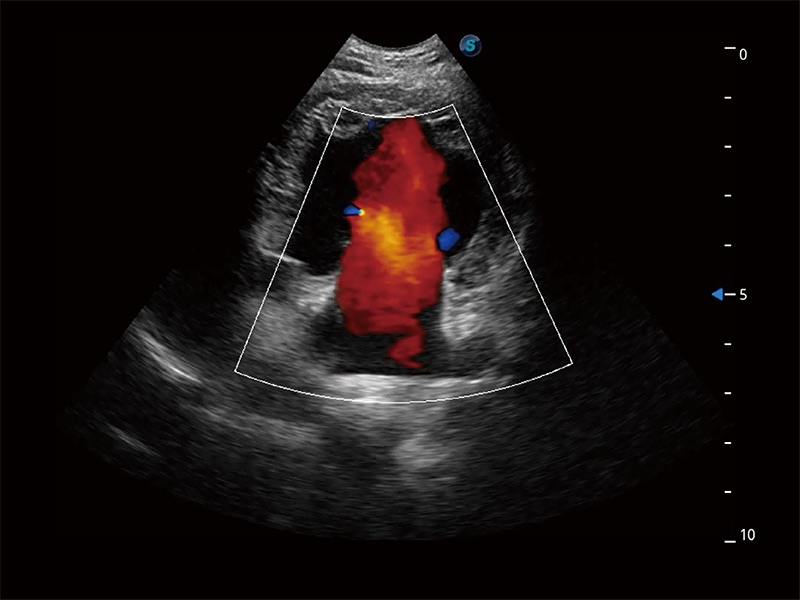

非线性融合造影成像充分利用谐波和基波信号,为难以观察的血流进行增强显像。可用于线阵、凸阵、微凸阵、相控阵探头。